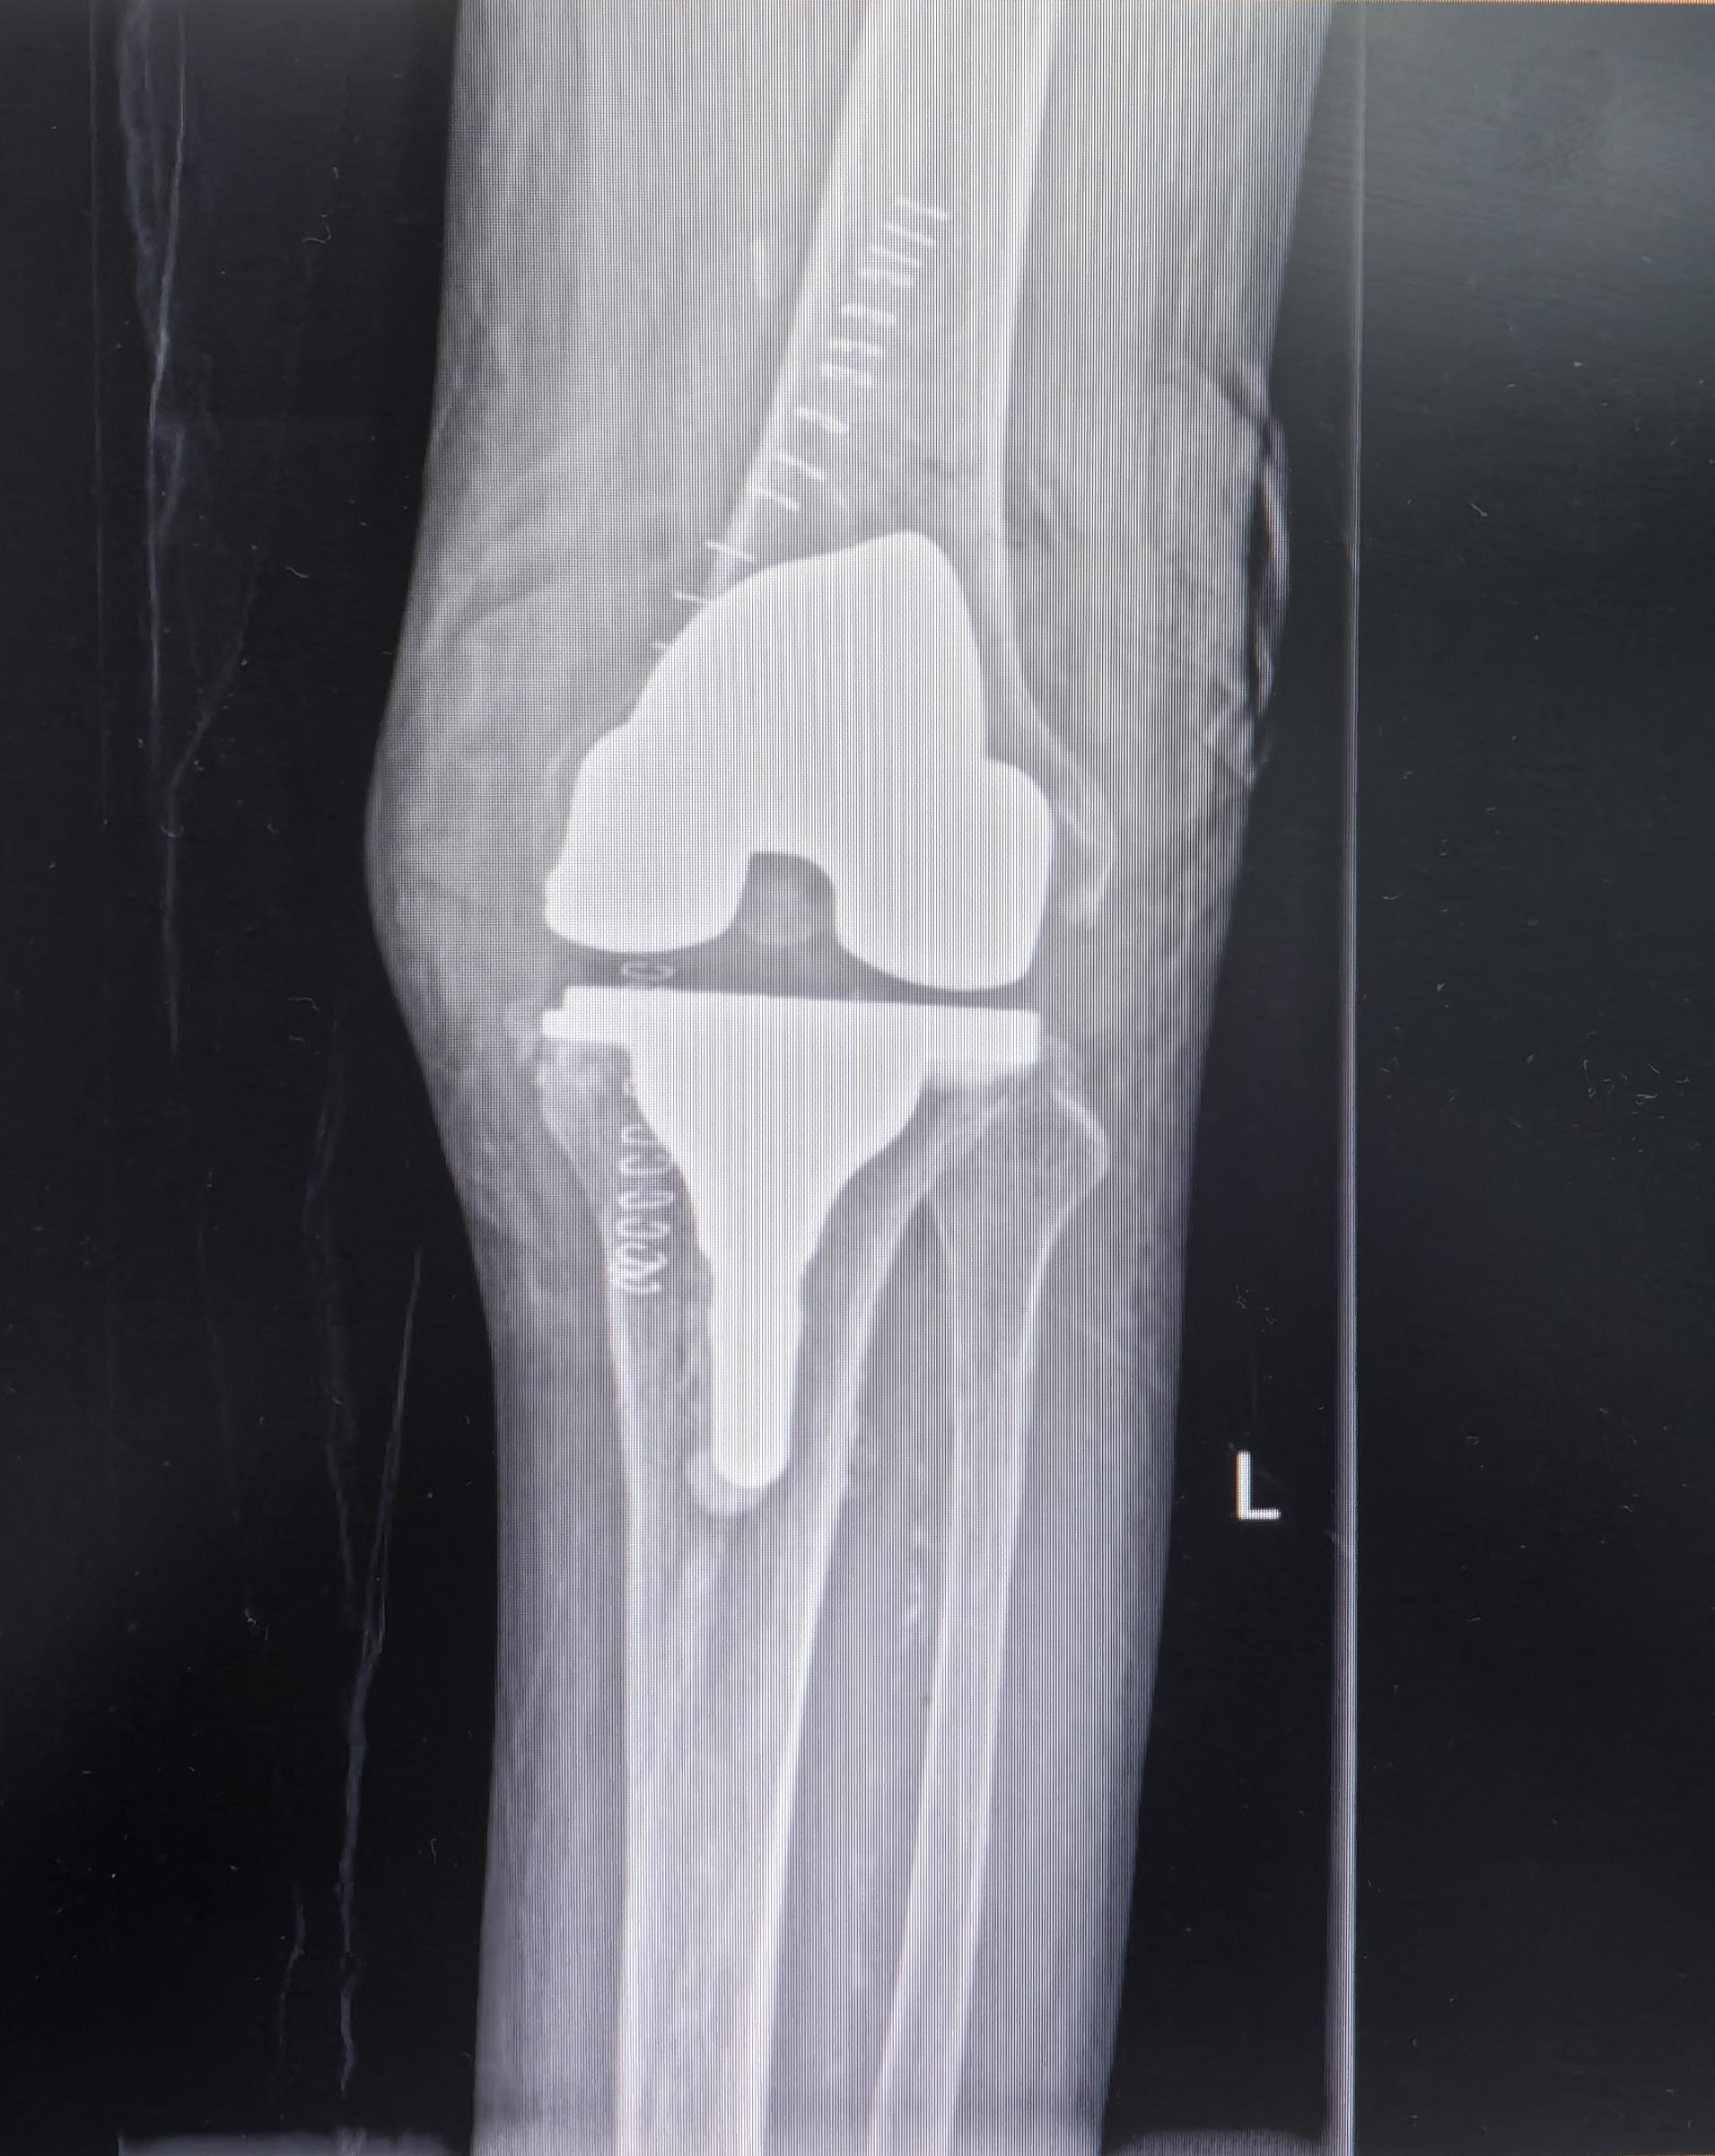

膝关节置换TKA.受罪多年的85岁老爷子,终于下定了决心。其实骨性关节炎到了这种地步,伸不直蜷不住,走路都困难,真是早做早受益。